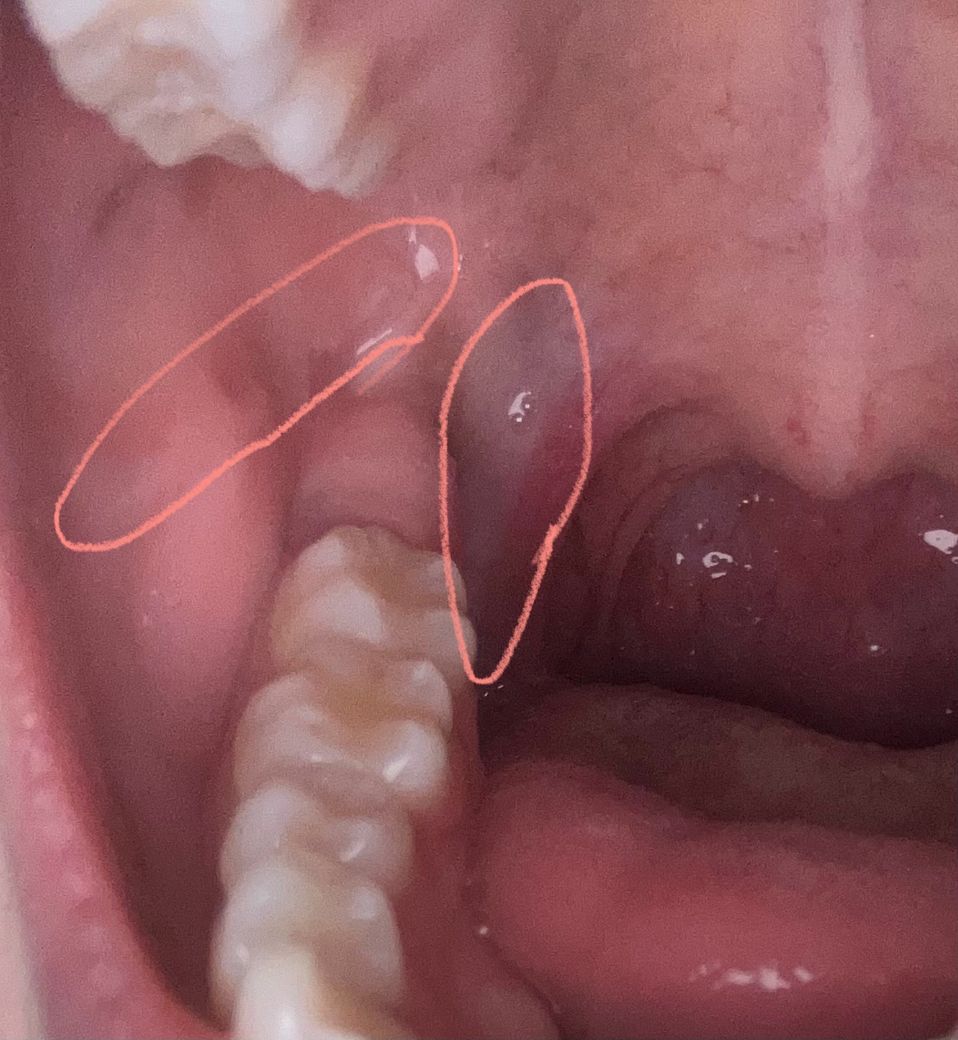

목 안쪽 흰색 이게 뭔가요 ?? 그리고 점막이 이어져있는게아니고 좀 떨어져있는건 왜 그런가요?

목 양쪽에 흰색으로 쭉 밑까지 있습니다 그리고 양볼이 백선이 생겨서 안없어지는데 그 안쪽까지 있어서 원래는 위아래가 붙어있어야하는것같은데 떨어져있는것같이 보여요 실제로 보면 더 심합니다 ㅜㅠ 이 두개가 뭔가요?

우선 단순한 백태나 염증이 아닌 곰팡이 감염(구강 칸디다증), 백반증(구강 백반증) 또는 편평태선과 같은 만성 점막 질환일 수 있어요. 특히 양쪽에 대칭적으로 나타나고, 쉽게 없어지지 않으며 표면이 하얗고 약간 거칠거나 벗겨지지 않는다면 병적인 변화일 가능성이 있습니다. 백선이라고 생각하셨던 부분이 실제로는 구강 점막에 생긴 진균성 질환이나 만성 자극성 병변일 수 있죠

점막이 위아래가 원래처럼 밀착되어 있지 않고 떨어진 것처럼 보인다는 건, 염증이나 병변으로 인해 조직이 위축되거나 형태가 변형되었을 가능성도 있습니다. 이는 단순 구내염 수준이 아닐 수 있기 때문에, 빠르게 구강외과 전문이 있는 치과, 또는 이비인후과 방문을 권해요. 조직검사나 진단을 통해 악성 변화 가능성까지도 감별할 수 있으니, 절대 방치하지 마시고 병원 진료를 꼭 받아보시길 바랍니다